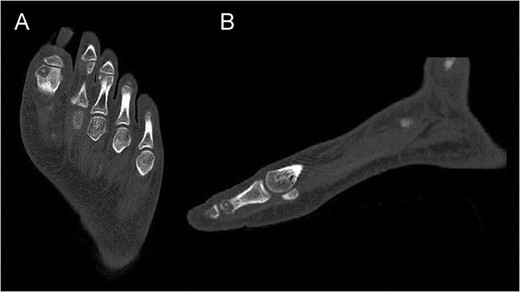

Preoperative CT of the proximal phalanx of the left hallux: axial (A), and sagittal view (B), showing the osteolytic nidus of the tumor with central calcification surrounded by a slight sclerotic halo: the standard image of OO.

CT of the proximal phalanx of the left hallux: axial (A) and sagittal view (B), showing the recurrence of the OO and its extension to the articular surface.